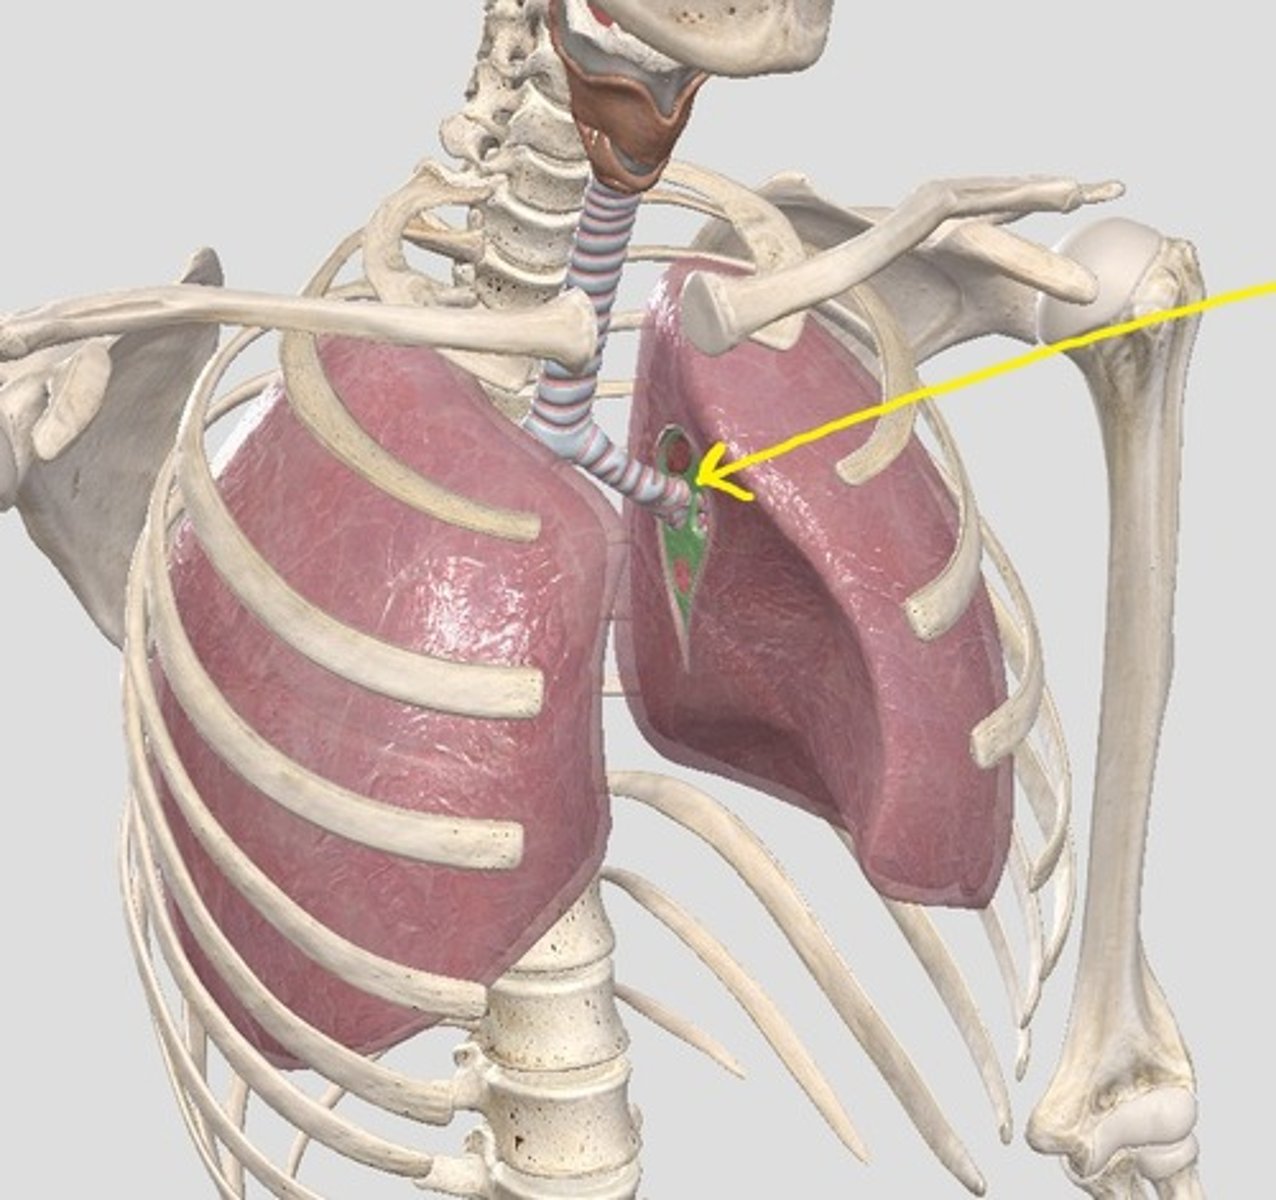

hilum of right lung

hilum of left lung

name the green portion

name the green portion

name the green portion

name the green portion

name this cartilage

name the ligament in this area

name this muscle